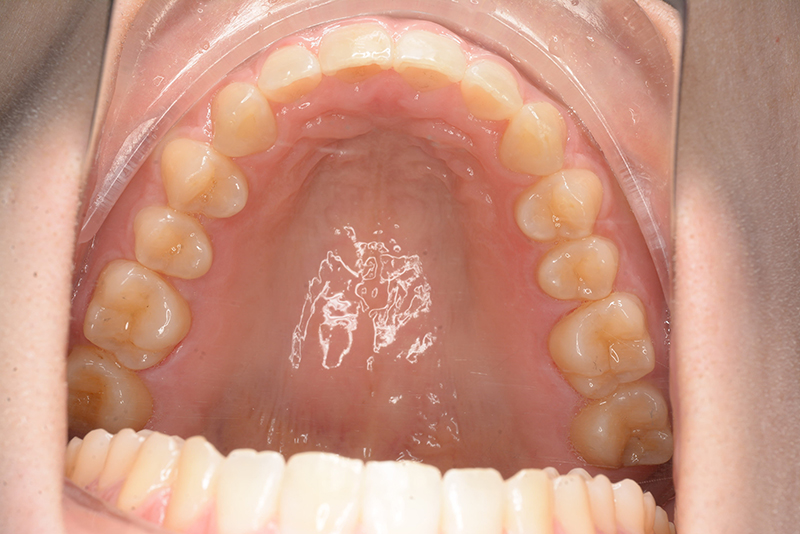

口腔内所見 大臼歯、犬歯関係はⅡ級で、上顎中切歯は舌側傾斜しており、over jet1.5mm,over bite 6.0mmいわゆるⅡ級2類であった。

批評・予后 上顎臼歯は軽度に近心傾斜しつつ、歯列遠心部には奥行きがあり、下顎歯列には叢生は認められず、スピー湾曲も軽度であること。また軟組織上の問題もないため、上顎歯列の遠心移動による治療が妥当だと判断した。治療後において上顎歯列の遠心傾斜と共に下顎はカウンタークロックワイズローテーションをしながら咬合の緊密化が得られた。